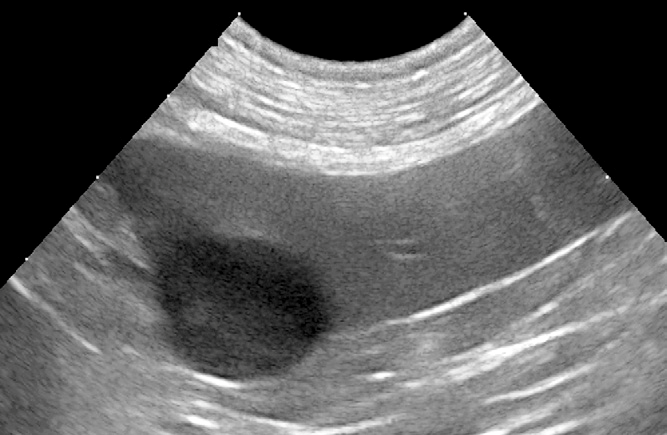

Radiology Support

Need a hand with radiographs, CT, MRI or US loops? We’ve got you covered. Our team provides detailed, high-quality reports to support you in managing your cases.

In addition to interpreting images, we can also provide imaging protocols for specialized CT or MRI studies (for example: urinary tract excretory contrast CT, lymphangiography, etc.). Let us know if you have questions about the imaging in advance.

Over the years, we’ve learned that imaging reaches its full potential when interpreted in context. That’s why for radiographs, CT, MRI, and ultrasound cases, our radiologist can collaborate with clinical specialists who can review the case in depth. After reviewing the images, the specialist can discuss the next steps with you—from further work-up to treatment planning.